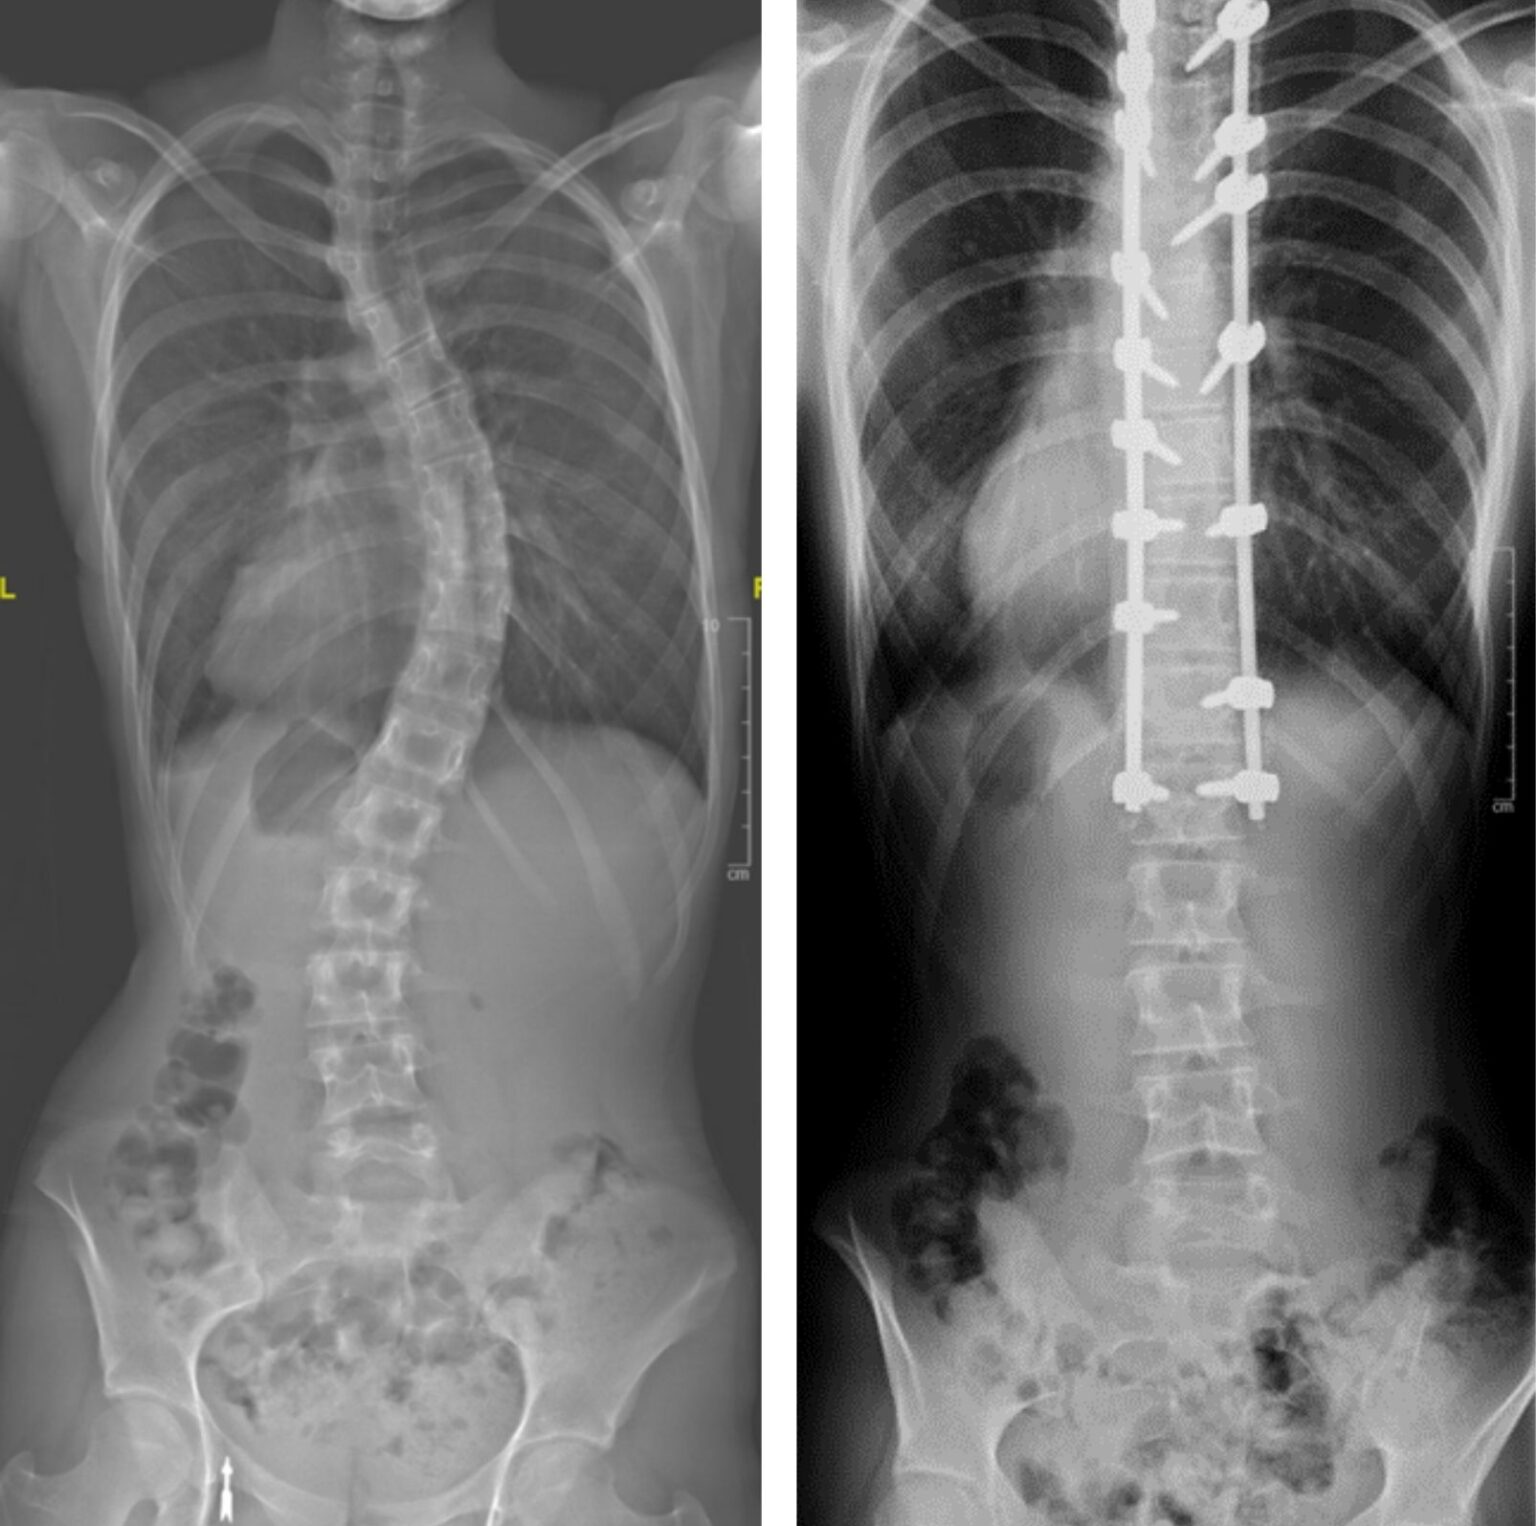

Severe Scoliosis Before And After Can You Still Play Sports With Scoliosis Which sports are safe to play? How does scoliosis affect athletes?. Running with scoliosis doesn't just affect teenagers. While there’s no evidence that any sporting activity can treat scoliosis, we do know that the condition can cause muscle weakness. Strong core muscles from exercise and sports are beneficial to your back, according to the scoliosis research society, an international organization. Can You Still Play Sports With Scoliosis.